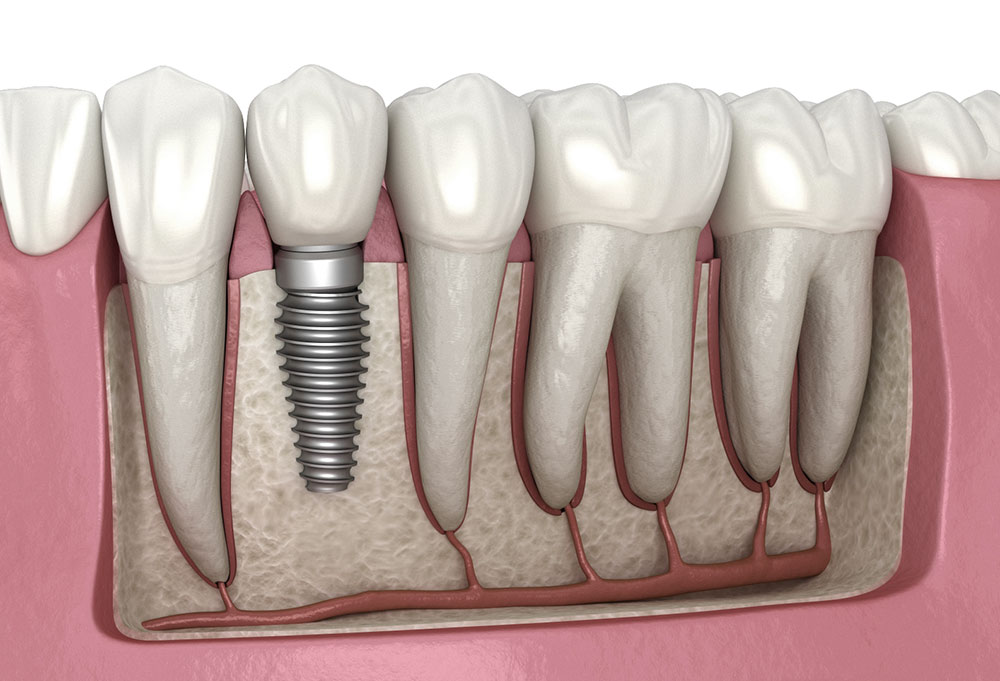

Un implant dentaire est une racine artificielle, généralement en titane, insérée dans l’os de la mâchoire pour remplacer la racine d’une dent naturelle manquante. Il sert de base solide pour fixer une couronne, un bridge ou une prothèse.

Les composants d’un implant

- 🔹 L’implant : vis en titane insérée dans l’os

- 🔹 Le pilier : connecte l’implant à la couronne

- 🔹 La couronne : partie visible qui imite la dent naturelle